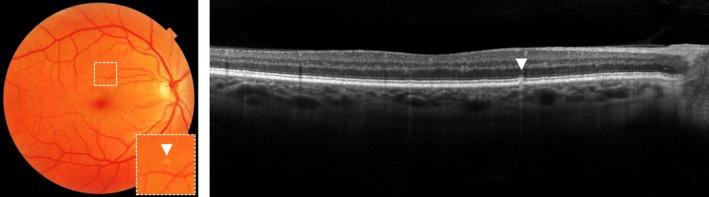

Age-related macular degeneration (AMD) is a degenerative disease of the macula, often leading to progressive vision loss. The rate of disease progression can vary among individuals and has been associated with multiple risk factors. In this review, we provide an overview of the current literature investigating phenotypic, demographic, environmental, genetic, and molecular risk factors, and propose the most consistently identified risk factors for disease progression in AMD based on these studies. Finally, we describe the potential use of these risk factors for personalised healthcare.

While phenotypic risk factors such as drusen and pigment abnormalities become more important to predict disease progression during the course of the disease, demographic, environmental, genetic and molecular risk factors are more valuable at earlier disease stages. Demographic and environmental risk factors such as age and smoking are consistently reported to be related to disease progression, while other factors such as sex, body mass index (BMI) and education are less often associated. Of all known AMD variants, variants that are most consistently reported with disease progression are rs10922109 and rs570618 in CFH, rs116503776 in C2/CFB/SKIV2L, rs3750846 in ARMS2/HTRA1 and rs2230199 in C3. However, it seems likely that other AMD variants also contribute to disease progression but to a lesser extent. Rare variants have probably a large effect on disease progression in highly affected families. Furthermore, current prediction models do not include molecular risk factors, while these factors can be measured accurately in the blood. Possible promising molecular risk factors are High-Density Lipoprotein Cholesterol (HDL-C), Docosahexaenoic acid (DHA), eicosapentaenoic acid (EPA), zeaxanthin and lutein.